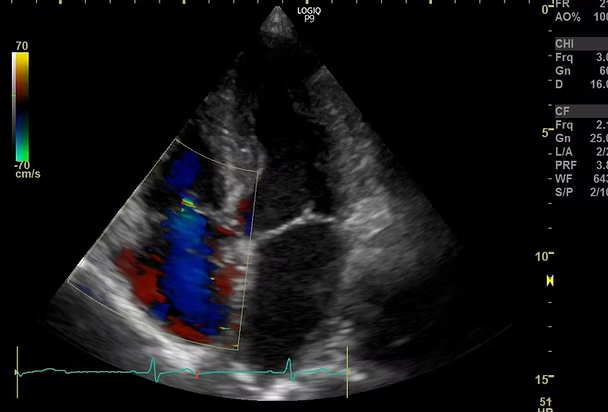

頸動脈エコー、心臓エコー、下肢静脈エコーの検査を行っています。頸動脈エコーは首の中にある頸動脈を観察し、動脈硬化のために血管が傷んでいないか、血液の流れが悪くなっていないかを調べる検査です。心臓エコーは心臓の大きさや心臓の筋肉の動きを観察することによって、心臓のポンプ機能が働いているかを調べます。下肢エコーは太ももからくるぶしにかけて静脈の流れが悪くなってないかを調べる検査です。いずれの検査も痛みのない、手軽で安全な検査です。

心臓エコー